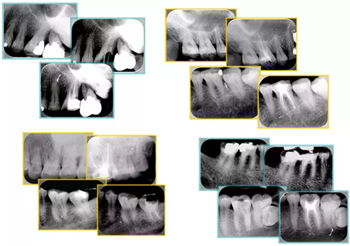

共有 4 張 X 線片,分別是術(shù)前、診斷絲 、主牙膠尖確認(rèn)、術(shù)后。

( 1 )術(shù)前:術(shù)前 X 線片用來了解牙齒的大概情況。術(shù)前預(yù)期為多根牙時 X 線片應(yīng)偏頭拍攝。

( 2 )診斷絲:根據(jù)術(shù)前 X 線片進(jìn)行開髓、根管的初步預(yù)備后,需要插入診斷絲,用來指示工作器械位置。常用 10 號或 15 號擴(kuò)大器作為診斷絲插入牙髓腔。

( 3 )主牙膠尖確認(rèn):通過術(shù)前預(yù)期和診斷絲診斷,明確工作長度、牙根走向,進(jìn)行根管預(yù)備。之后應(yīng)進(jìn)行主牙膠尖(中銼)確認(rèn),已明確根管是否適合充填。

( 4 )術(shù)后:觀察治療效果。

圖為根管充填術(shù)后 X 線片。圖中可見,根管充填較好。右下圖有白色小點(diǎn),為側(cè)方加壓導(dǎo)致糊劑擠出所致,表明根管充填比較致密。

常見不良根管充填物有干髓、塑化、塑化 + 根充和不良根充。

上圖為干髓治療后牙齒,齲齒疏通后進(jìn)行根管充填。

如圖為塑化加根充處理后牙齒 X 線片。

常見有修復(fù)性鈣化和增齡性鈣化。下面為根管鈣化 X 線片。

右圖及下圖為器械折斷的 X 線片。箭頭處示折斷器械。

右圖箭頭處示臺階形成。